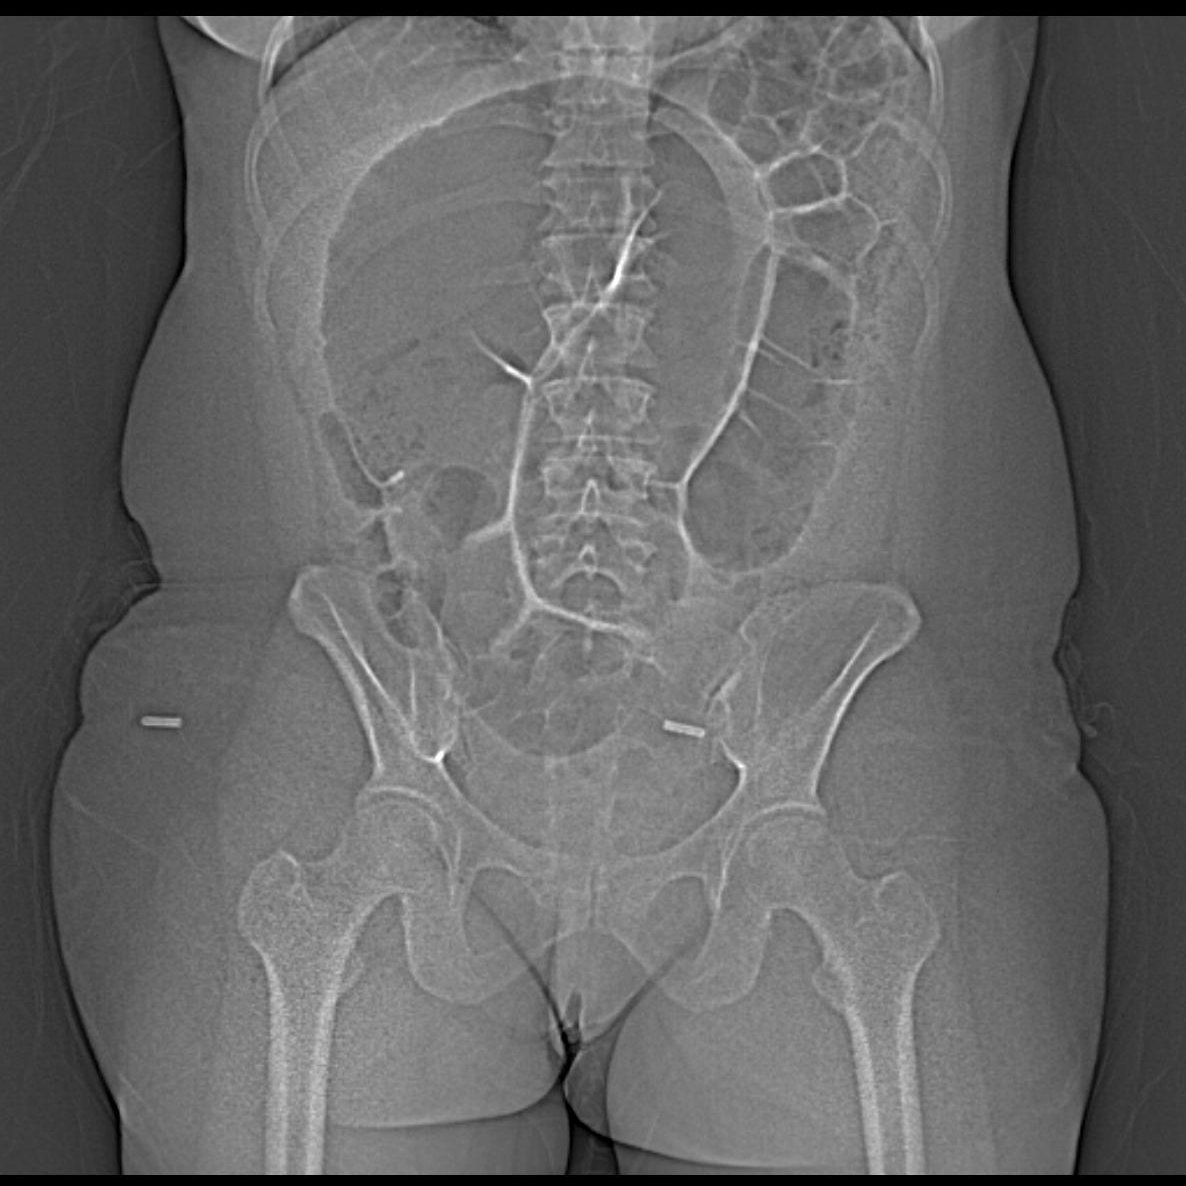

I wish I had a KUB but scout will do! 44-year-old female patient presenting with decreased bowel movements and abdominal distention... what is the name of this sign? GIFs only please! @BrighamRad @FOAMrad @SAR_RFS @futureradres @ARRS_Radiology @Abdominal_Rad @CBRadiologia